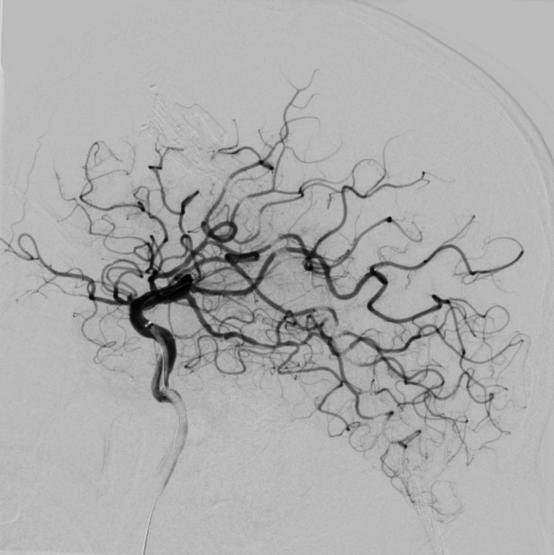

在转运的过程中,患者症状持续加重,完全失语、右侧肢体全瘫同时意识逐渐模糊。糟糕,一定是左侧颈内动脉闭塞后血流缓慢继发颅内血栓形成。时间就是大脑,为挽救李大哥的生命,民航总医院卒中团队高效运作起来,神经内科、血管介入科、麻醉科迅速完成了患者的转运、麻醉及造影。如术前所料,患者左侧颈内动脉C6段闭塞(图4、5),左侧大脑中动脉M2段血栓形成(图6)。一个一个环环相扣的动作,一个一个精细无间的配合,血管介入科团熟练的完成了取栓支架就位(图7)、取出大脑中动脉血栓、植入颈内动脉支架(图8)等一系列操作,成功的开通了血管,恢复了颅内的血流(图9、10)。

图10